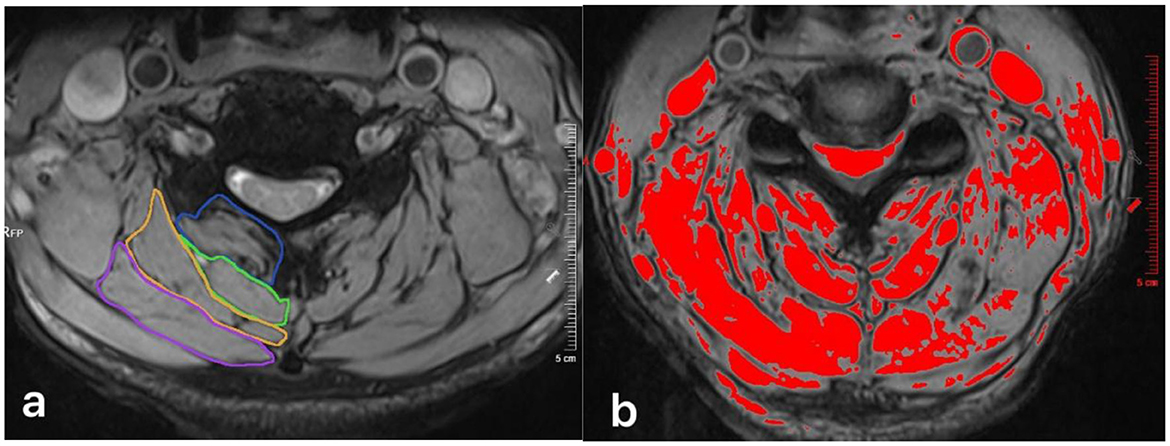

Figure 5

(a) Measurement of pre-operatively total CSA at C4/5 level for the multifidus (MF, blue circle), semispinalis cervicis (SC, green circle), semispinalis capitis (SCap, orange circle), and splenius capitis (SpC, pink circle). (b) Thresholding technique was used to mark the pre-operative FI and calculate the fCSA.